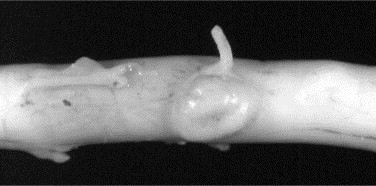

Cryptococcus neoformans is a saprophytic fungal organism that can cause systemic or focal disease. Transmission occurs through inhalation of the organism that lives in the soil or bird excrements. CNS signs are reflective of meningitis or focal granuloma formation within the brain parenchyma. Fungal masses within the extradural space cause secondary compression (Figure 51-2 ).17 Cryptococcal infection can cause focal spinal cord disease in some cats. The mean age for cats infected with Cryptococcus is 6 years; however, the age range can vary.18, 19 Approximately 58 per cent of cats diagnosed with Cryptococcus spp. were considered primarily outdoor cats.18

Figure 52-2.

Cryptococcus neoformans infection can cause focal spinal cord disease in cats. This picture depicts a fungal granuloma present on the spinal cord.